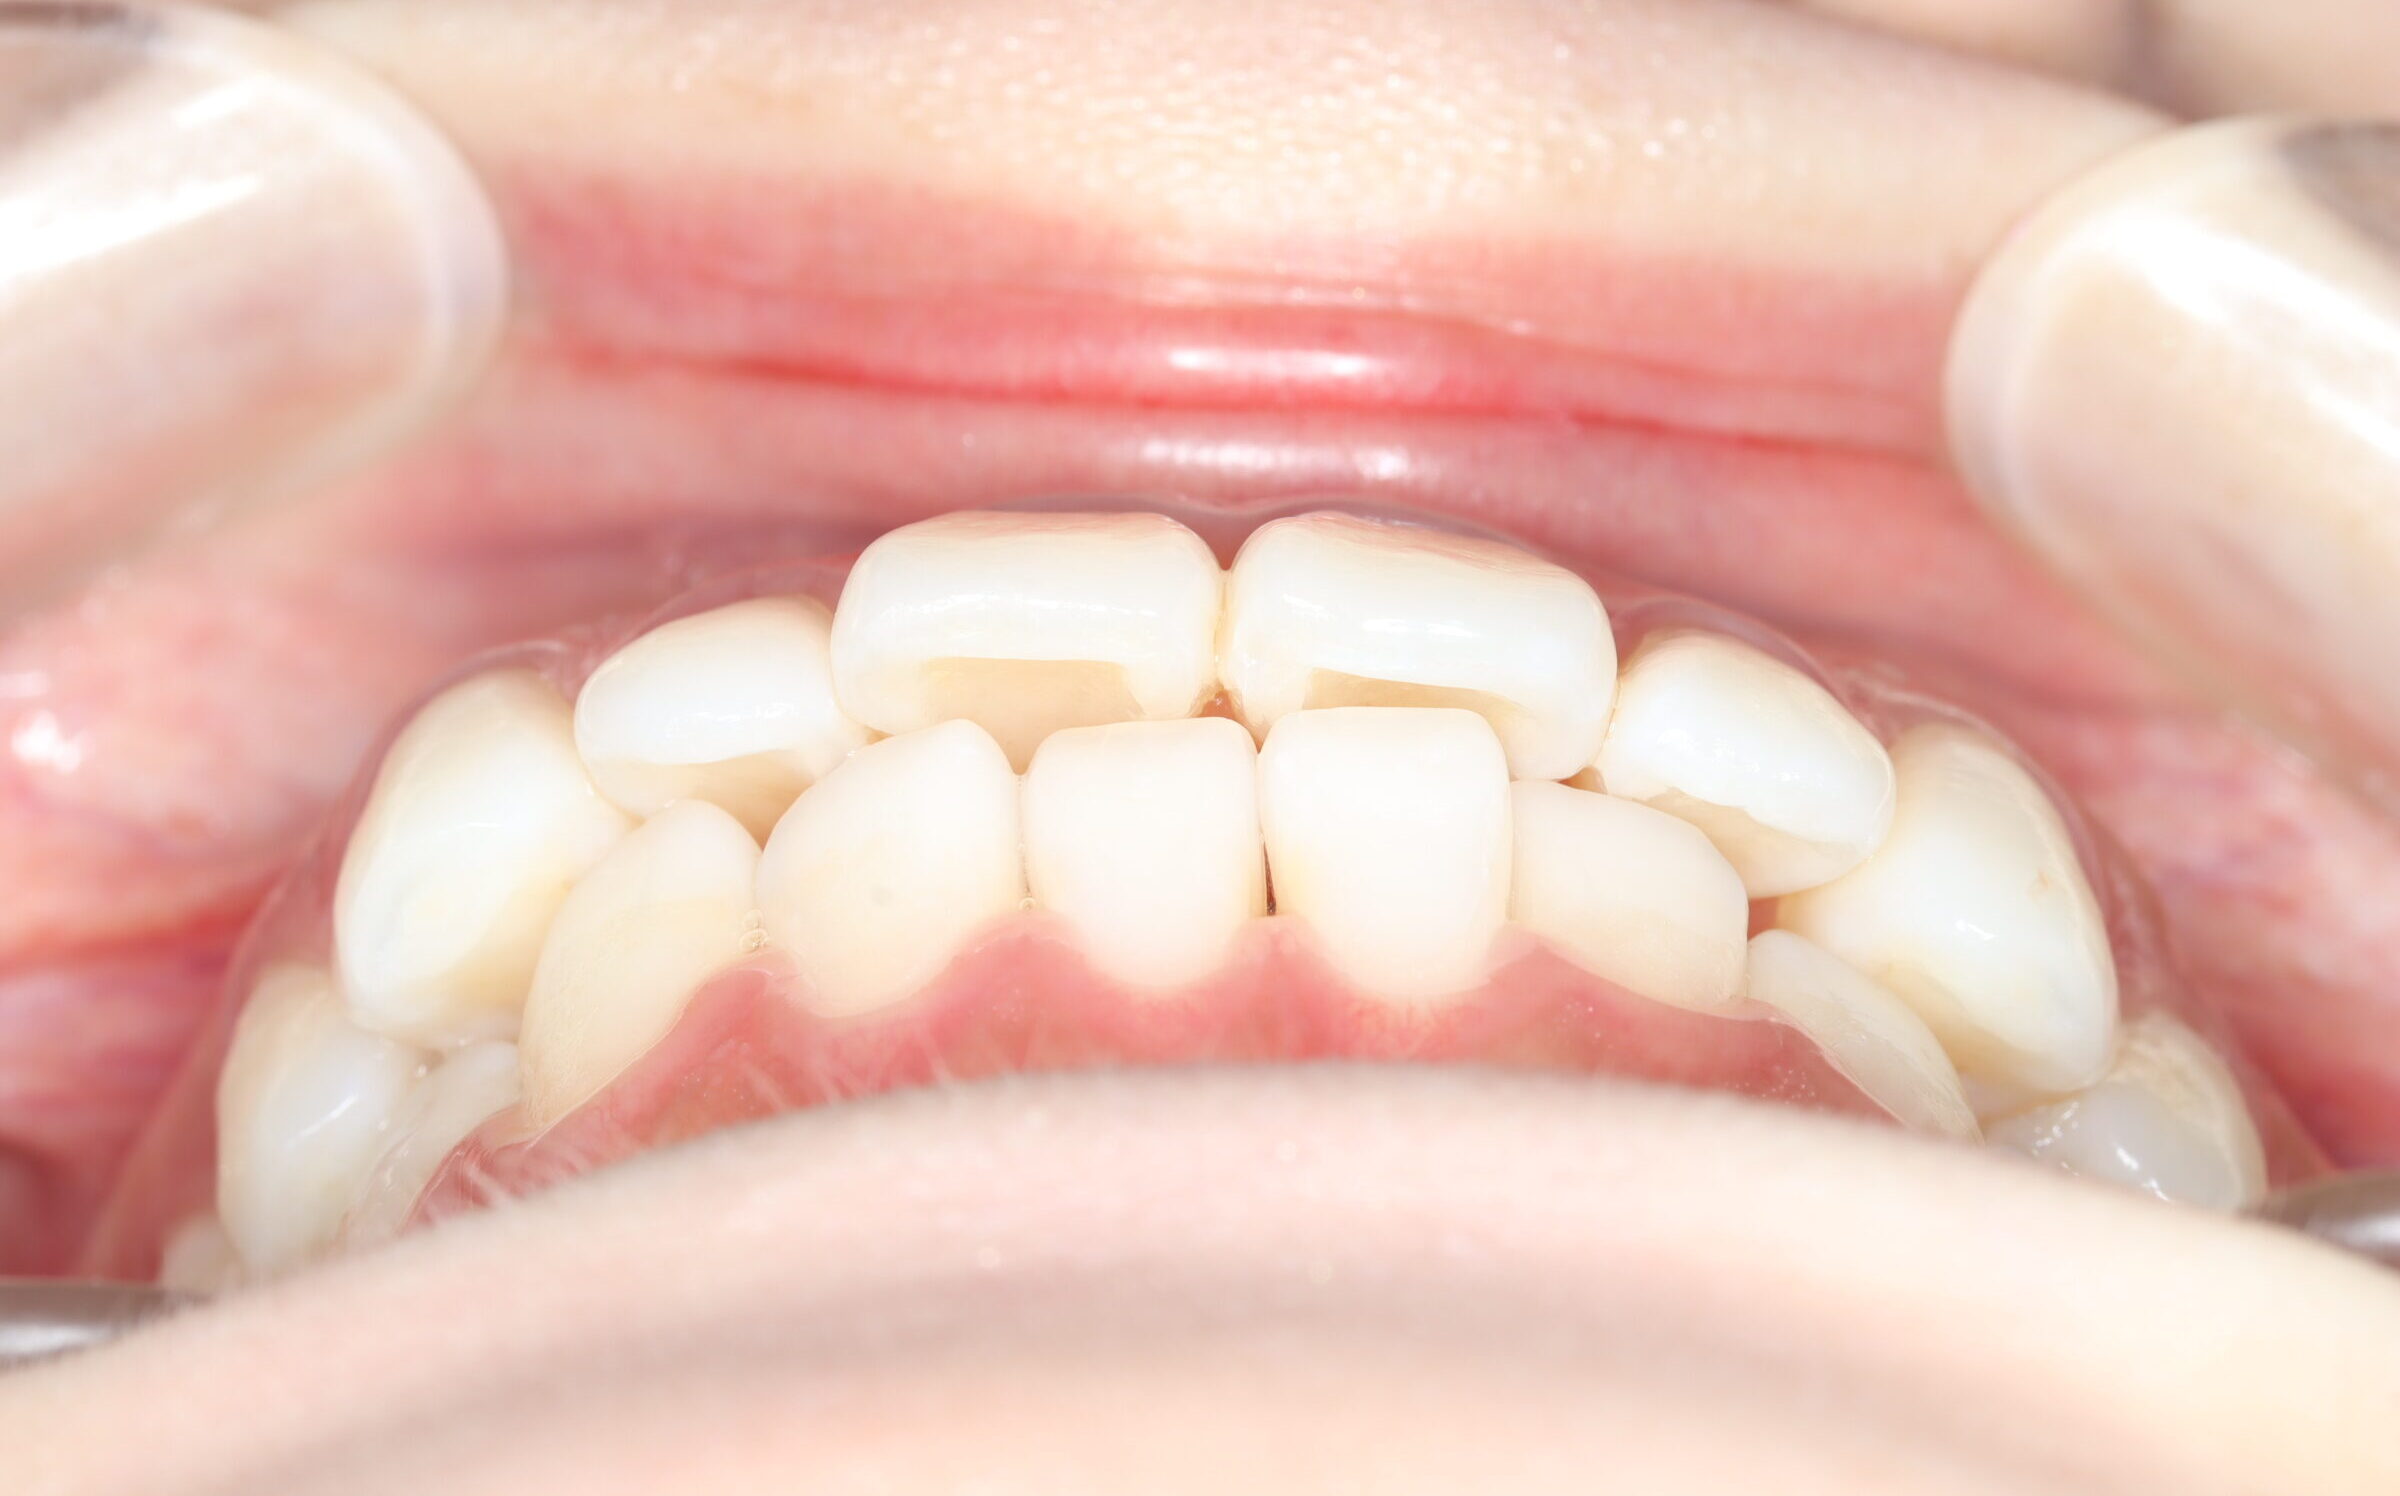

口腔内の変化

![]() | ![]() | ![]() |

| ↓ | ↓ | ↓ |

| 治療前 | 骨格的には受け口の患者さんですが、上顎前歯の唇側傾斜が大きく、患者さんとしては出っ歯だと思われていたパターンです。 元々口元の突出感はほとんどなかったため、歯を抜かずに上下顎ともに歯列を後方に移動させることにより主訴を改善させることとしました。 |